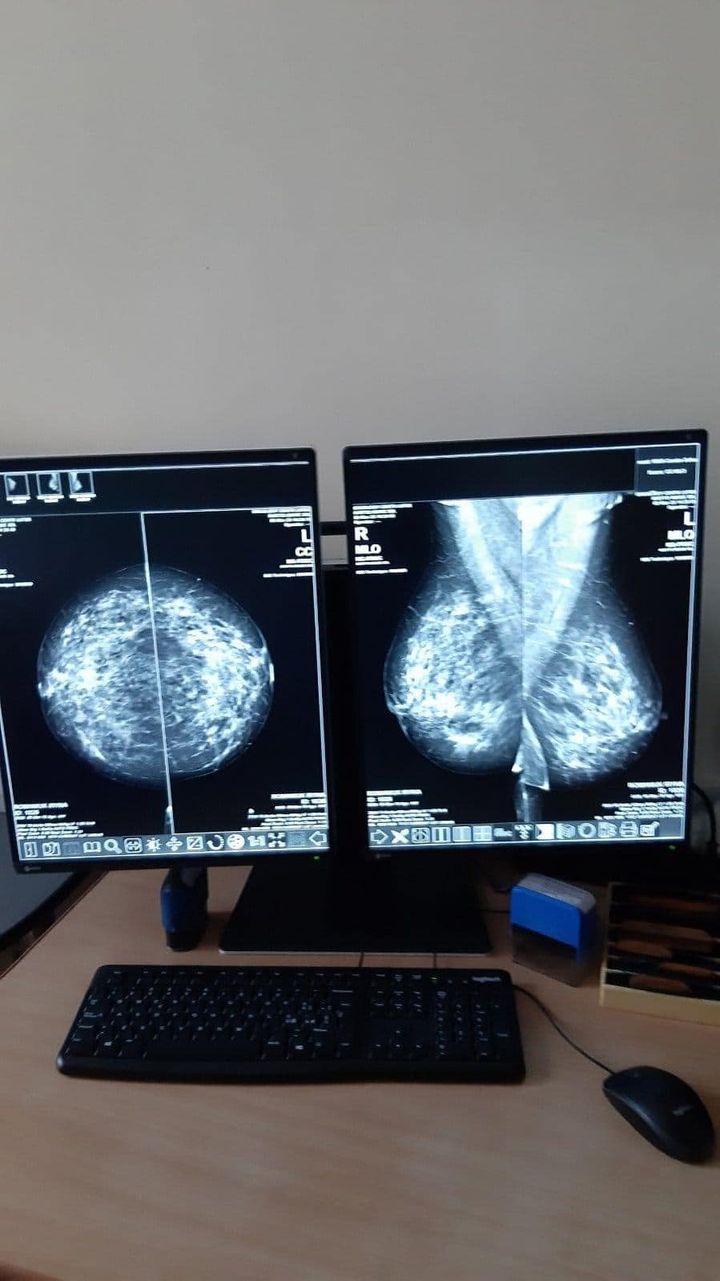

У Волинському обласному медичному центрі онкології встановлено GIOTTO IMAGE 3DL. Це сучасна цифрова мамографічна система, максимально зручна не лише для пацієнтів, але й для рентгенологів завдяки ергономічному дизайну та зрозумілому інтерфейсу користувача.

Програмне забезпечення Rafaello розроблений для роботи з інтенсивними робочими процесами мамографії: швидкі експозиції, миттєве відображення, настроювані протоколи збору даних та розширені інструменти візуалізації.

Функція визначення структури і мікрокальцинатів всередині щільних утворень(навіть імплантів)